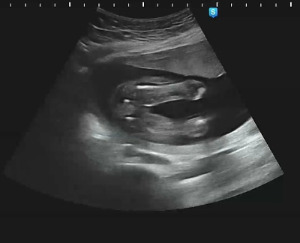

16주, 성별 확인의 순간

통상 16주 정도 되면 태아가 특별히 허벅지 사이를 가리고 있지 않는 이상, 성별 확인이 가능한데 우리 역시도 16주쯤에 성별 확인을 받았다.

KakaoTalk_20230419_003652110.jpg 까꿍이 다리 사이 초음파 사진!